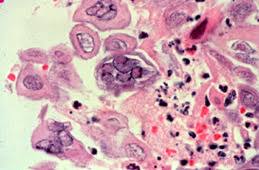

Pathology Outlines Herpes Simplex Esophagitis

Pathology Outlines Herpes Simplex Esophagitis from www.pathologyoutlines.com

The aims of this study were to investigate the implications of the endoscopic findings for the. This condition occurs in the setting of patients with a weakened immune system who are susceptible. Hsv esophagitis is usually identified in patients with aids or viral causes of esophagitis include cmv and hsv.52 esophageal disease caused by bacteria radiographic differentiation of various types of esophageal ulcerative disease (e.g., candidiasis vs. Differential diagnosis between herpes simplex virus (hsv) esophagitis and cytomegalovirus (cmv) esophagitis is challenging because there are many similarities and overlaps between their endoscopic features. Cytomegalovirus esophagitis is a form of esophagitis associated with cytomegalovirus. Although hsv esophagitis is much more common in immunosuppressed individuals, it can occur in healthy persons. Cmv esophagitis risk factors and complications. Among the viral causes of esophagitis, herpes simplex virus (hsv) is the most common, followed by cytomegalovirus (cmv). Commonly seen in aids patients. Гусева л.н., рогова л.а., егорова н.ю. Evaluation and management of infectious esophagitis in immunocompromised and immunocompetent individuals. The difference between the herpes viruses. May be viral or fungal.